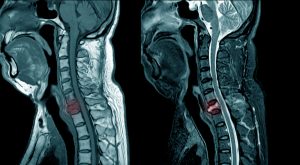

La región lumbar (columna baja) es la más comúnmente afectada, seguida de la cervical. Los discos torácicos (espalda media) rara vez se ven comprometidos. Puede acompañarse de sensaciones de hormigueo, entumecimiento o debilidad en el glúteo, el muslo, la pantorrilla o el pie. El dolor suele agravarse con maniobras que aumentan la presión en el disco, como toser, estornudar o hacer esfuerzo. Un signo de alarma que requiere atención médica inmediata es la pérdida de control de esfínteres (vejiga o intestino) o una debilidad muscular progresiva significativa, lo que podría indicar un compromiso severo de las raíces nerviosas. Para confirmar el diagnóstico, localizar con precisión la hernia y descartar otras patologías, se suele recurrir a estudios de imagen. La resonancia magnética es la prueba de elección, ya que muestra con claridad los tejidos blandos, los discos, los nervios y el grado de compresión. Una tomografía computarizada puede ser una alternativa.